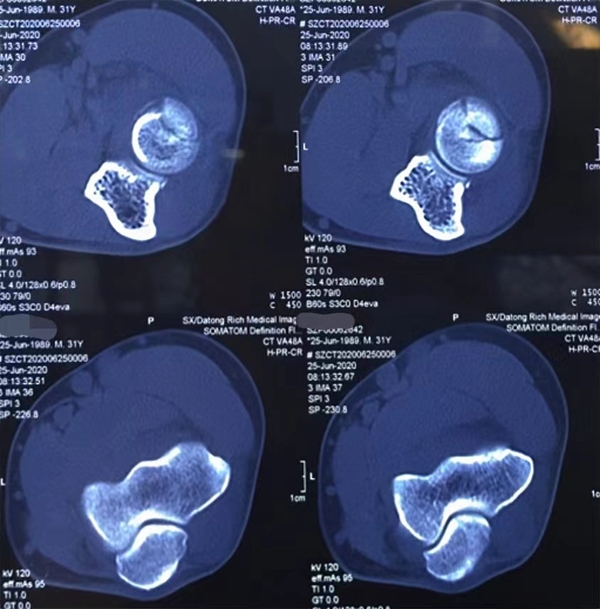

山西医大二院分型,根据CT分型:

依据桡骨头赤道线分型,大部分关节内的桡骨头骨折(Mason2型),都会累及桡骨头的前外1/4。分为:

① 桡骨头前半球骨折;

② 桡骨头后半球骨折。

图2 桡骨头骨折2型赤道前半球骨折

图7 桡骨头2型 赤道半球骨折

1、CT桡骨头横切面9点至3点作为赤道线,依据桡骨头赤道线分型分为:

①桡骨头前半球骨折;②桡骨头后半球骨折。